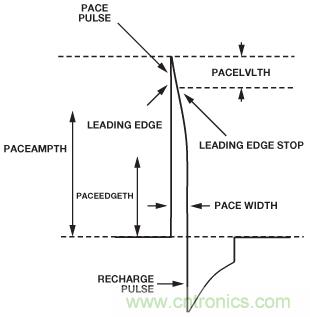

多數(shù)起搏脈沖都有著超快的上升沿。起搏器輸出端測得的上升時(shí)間一般為100 ns左右。當(dāng)在皮膚表面測量時(shí),受起搏導(dǎo)聯(lián)線電感和電容的影響,上升時(shí)間會(huì)略低。皮膚表面的起搏偽像大多為10 μs或以下。作為內(nèi)置保護(hù)機(jī)制的復(fù)雜器件,起搏器可能會(huì)產(chǎn)生高速毛刺,雖然不會(huì)影響心臟,但會(huì)影響起搏器檢測電路。

圖6所示為理想起搏偽像的示例。正脈沖的上升邊沿很快。在脈沖達(dá)到最大幅度之后,會(huì)發(fā)生容性下降,然后出現(xiàn)后沿。之后,在起搏脈沖的再充電部分,偽像會(huì)改變極性。之所以需要該再充電脈沖,是為了使心臟組織保持凈零電荷。對于單相脈沖,離子會(huì)在電極周圍聚集,結(jié)果產(chǎn)生的直流電荷可能導(dǎo)致心臟組織損壞。

圖6. 理想型起搏偽像